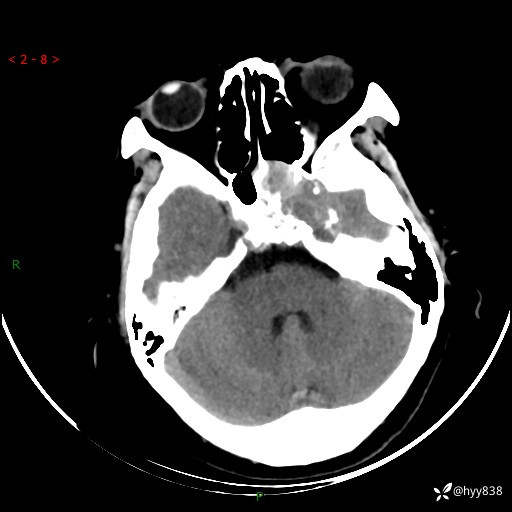

老年女性,视力下降3年。鞍区钙化性肿块,鉴别诊断有哪些---(有结果)

简要病史:患者3年前无明显诱因左眼出现视力下降,出现视物模糊,无头痛,无头晕,无恶心、呕吐,无意识障碍,无肢体麻木及抽搐,无心慌、胸闷,无腹痛、腹胀等不适,无旋地转感。个月前右眼视力下降,患者视物模糊逐渐下降,自诉看东西有雾感。在当地医院眼科就诊,症状无好转,行头部MR提示:鞍区肿物。现患者为求诊治来我科就诊,在当地市中医医院行头部CT:提示鞍区占位。患者现求进一步诊治来我院就诊,门诊以“鞍区肿物”收入我科。 患病以来,患者精神、饮食、睡眠尚欠佳,大小便如常,体力体重无明显变化。

临床诊断:鞍区肿物

颅脑CT平扫